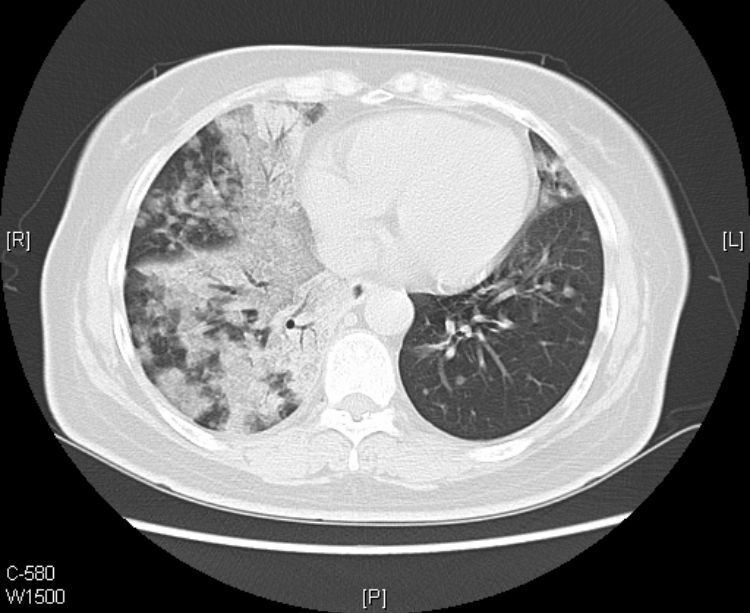

接着看她往下的CT层面:

从CT片上我们可以看到:老人的黏液腺癌还发生了气道转移。

CT提示气道播散的征象包括:多发小叶中心结节,分支模糊呈树芽征,通常边界不清,可见磨玻璃影。

1.气道播散形成的结节呈聚集分布,可以融合增大,有时也可形成空腔。

2.当转移灶远离原发灶时,所形成结节多分布于肺叶下部。